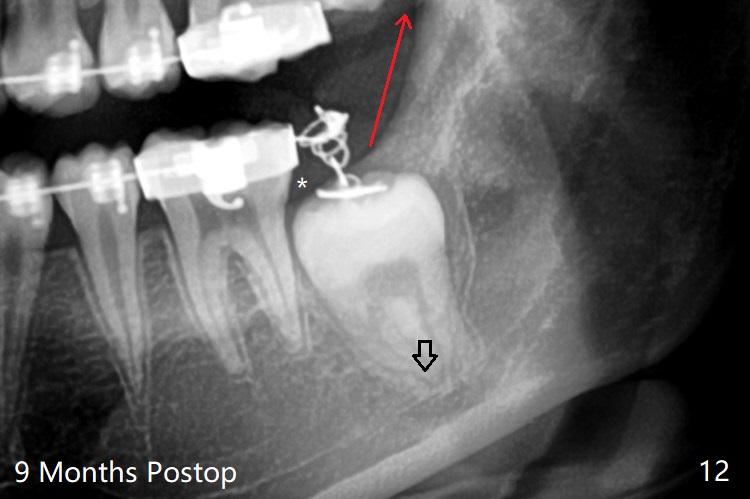

Treatment planning of surgical access to the impacted 7 (Fig.1) before CT analysis (to be canceled due to finance) include extraction of 8 (Fig.2) and removal of the bone coronal to 8 (Fig.3 red) so that there will be no bony block to 7 eruption (Fig.4). Place PRF or collagen plug in 8 socket to facilitate healing (Fig.3). Attach a retraction chain to the occlusal or buccal surface of 7 (Fig.6 pink) whenever it is convenient in term of hemorrhage and access (as mesial as possible). Remove 16 niti wires for brushing when the patient arrives. Cut 18 ss wire longer in the LL end (Fig.6 green to be bent to hook power chain (yellow)). Incision is shown as red in Fig.5. After 3 month delay, the thick buccal plate is removed from LL8 (1st) and 7 (2nd in sequence, as compared to Fig.2) to expose these unerupted teeth. In fact CT is not taken to decrease budget on the divorcing parents. A retraction chain is placed before extraction of LL8 with an intention to reduce hemorrhage (Fig.7). Although extraction requires several sectioning of the tooth, hemorrhage is mild to moderate. Instead of PRF and sticky bone (as compared to Fig.3), Osteogen plug is placed in the socket (Fig.8 OP). The bony septum between the 2 sockets is intentionally kept in place (*). 事实的确这样发生(图九:*)。埋伏牙不仅上移(^),而且远中移动(>),因为牵引方向(红虚线(橡皮筋),挂在上牙弓丝(图九:20ss:图十:18ss(之前))远端勾,积极牵引三个星期)。下次左上7放置舌侧纽扣,让病人更换橡皮筋。其实纽扣粘不住,上牙弓丝远中勾也不现实,只能使用橡皮筋挂在左上6,经常断。术后6个月,左下7继续上移(图十一)。这种低效率牵引仍然有效,牙齿继续上移,牙根长长(图十二:空箭头),但是受到左下6远中阻挡(*),所以下次在左上7咬合面装置舌侧纽扣和closed spring,改善牵拉方向(红箭头)。